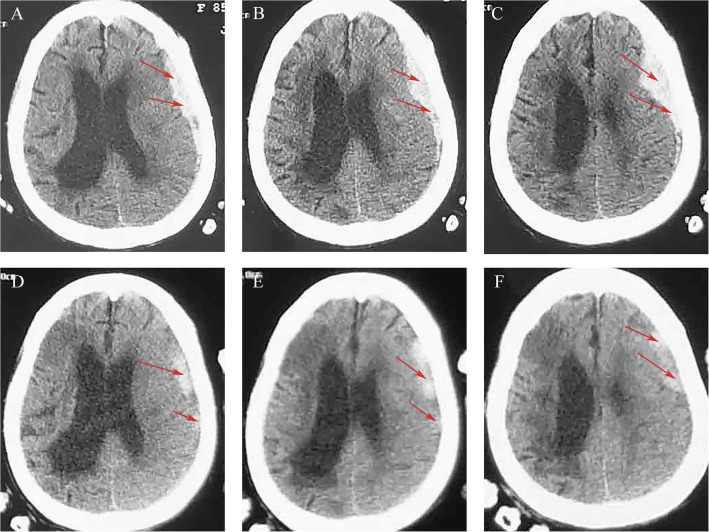

Case presentation: We selected five patients with sASDH who received a treatment regimen of atorvastatin plus low-dose dexamethasone without surgery. We then observed the clinical and radiological features during treatment and follow-up. The PubMed database and Google Scholar were retrieved for literature regarding the efficacy and safety of conservative treatment in patients with ASDH/sASDH. We extracted information including authors, sample size, gender, number of patients (death, poor prognosis, delayed surgery), and risk factors.

Results: Of the five patients, all patients who refused surgery for various reasons were resolved after treatment with atorvastatin plus low-dose dexamethasone for their conditions. No hematomas recurred or progressed during an at least 6-month follow-up. We identified 6 studies after searching the database; a total of 1374 patients (F:M = 3:7) with ASDH/sASDH received initial conservative treatment. The pooled results showed that 13.1% of patients who initially received conservative treatment deteriorated and required delayed surgical treatment. Of 1374, the overall incidence of poor prognosis was 19.2%, and 7% of patients eventually died.